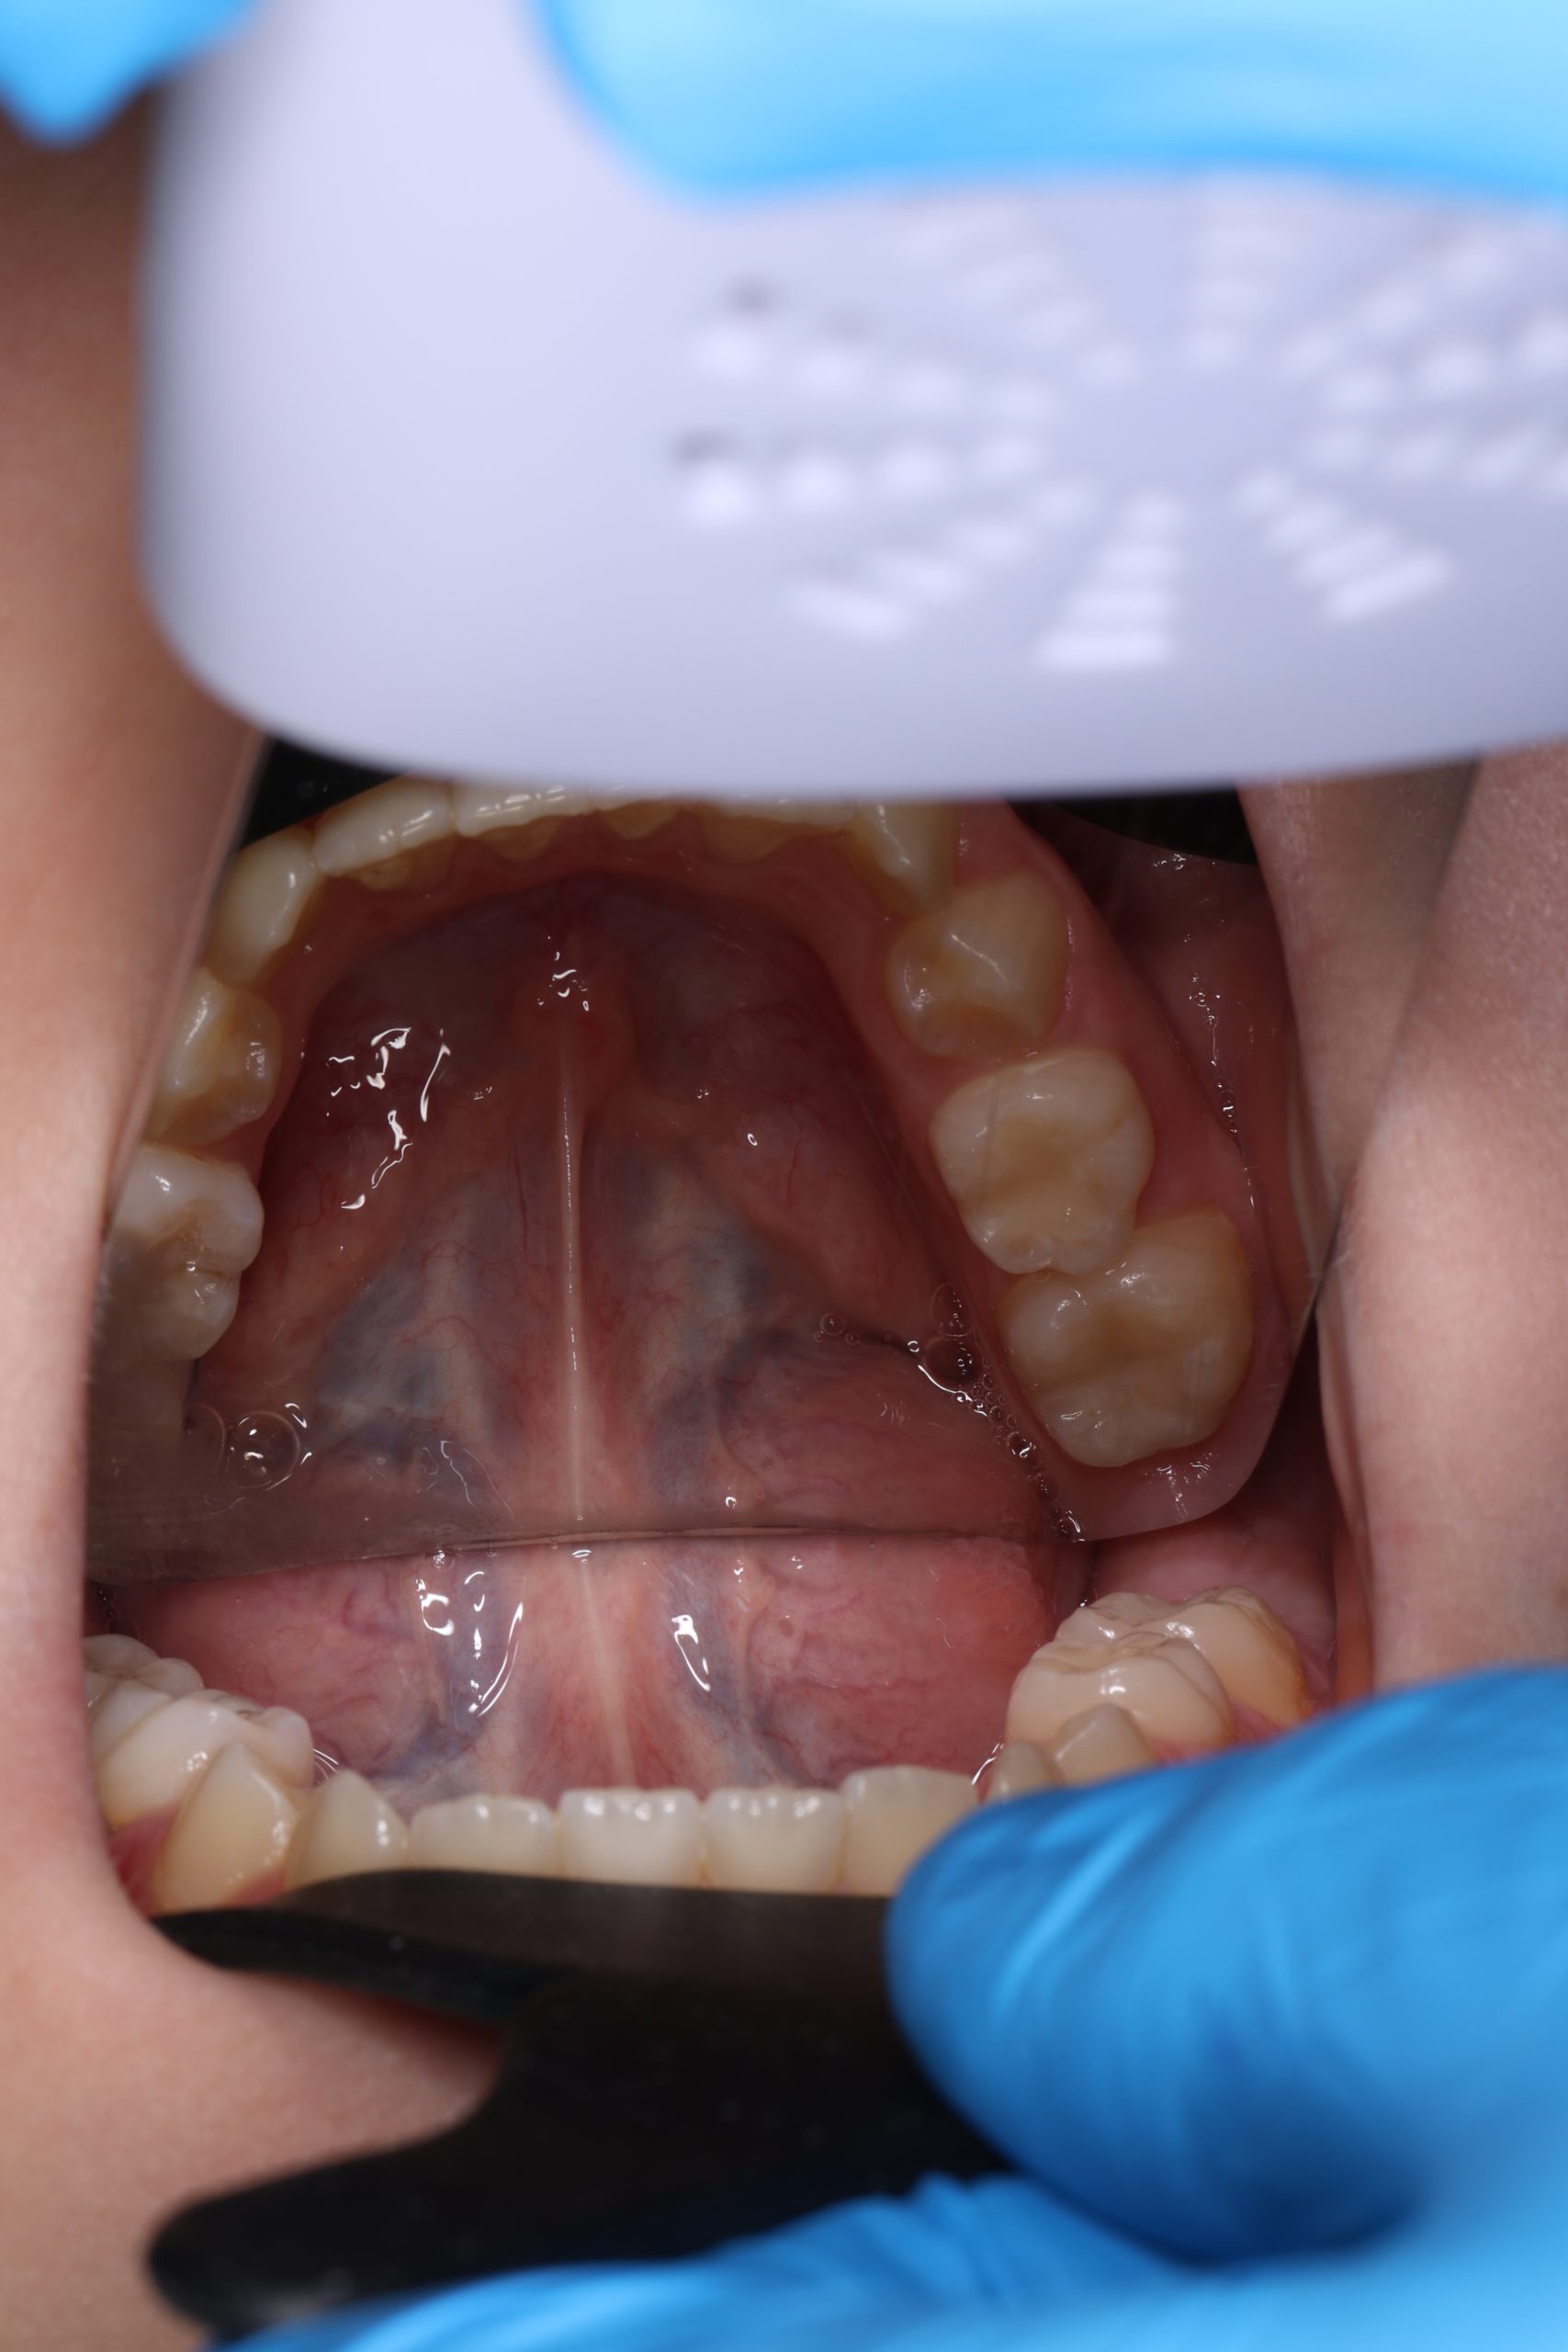

- Detailed Examination

We examine the condition of teeth, gums, and bite. - Plaque Disclosure with Special Indicators